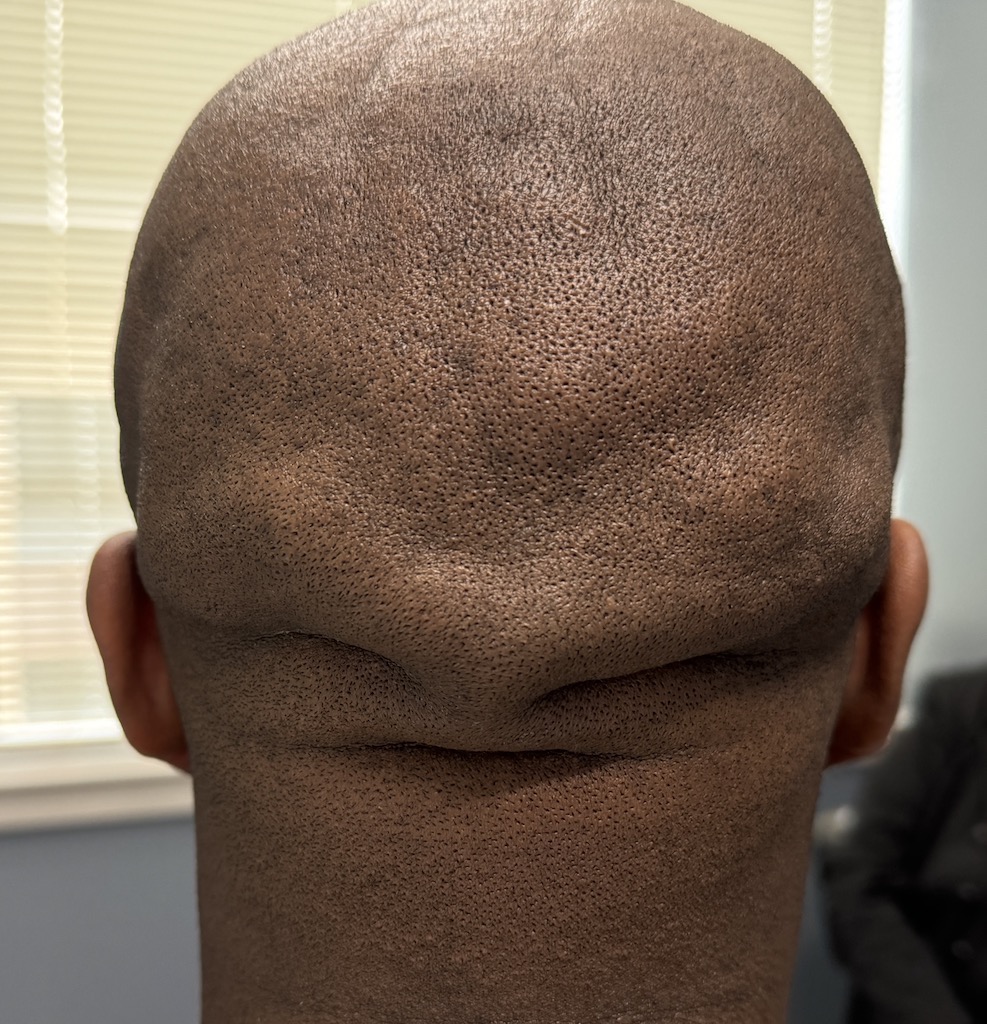

Patient 129

Desire for reduced width/convexity on the sides of his head.

Head narrowing using a temporal muscle transposition technique seen one day postop. He also had an concurrent occipital skull reduction done hence the tape over his incision.

Desire for reduced width/convexity on the sides of his head.

Head narrowing using a temporal muscle transposition technique seen one day postop. He also had an concurrent occipital skull reduction done hence the tape over his incision.